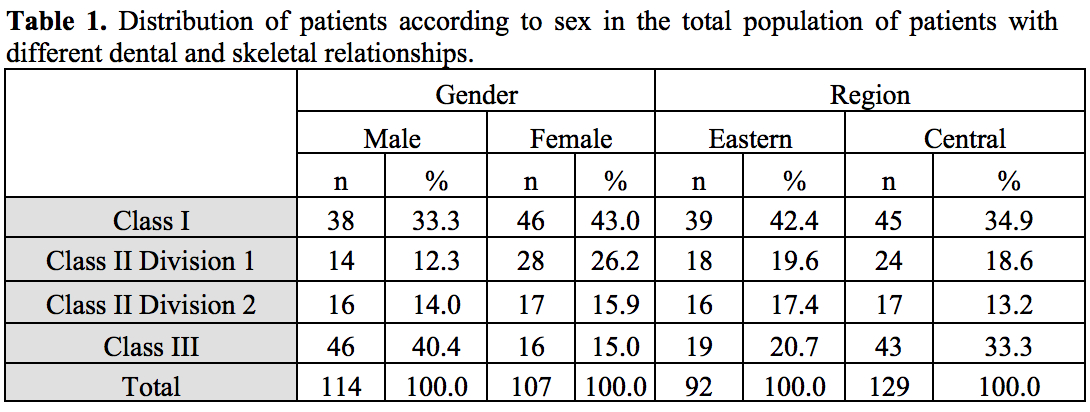

Methods: 221 lateral cephalometric radiographs of patients aged between 16–26 years (male [n=114] and female [n=107]) belonging to central and eastern regions of Saudi Arabia was taken from Orthodontic clinics database among Riyadh and eastern regions, Saudi Arabia. OnyxCeph3TM (Image Instruments GmbH Olbernhauer Str. 5 D 09125 Chemnitz Germany) digital software was used to analyze the dentoskeletal classification of the sample as Class I (n=84), Class II Division 1 (n=42), Class II Division 2 (n=33), Class III (n=62). Burstone analysis of six linear measurements for facial soft tissue thickness (FSTT) was used. All statistical analyses were set at a significant level of when (P<0.05).

Methods: 221 lateral cephalometric radiographs of patients aged between 16–26 years (male [n=114] and female [n=107]) belonging to central and eastern regions of Saudi Arabia was taken from Orthodontic clinics database among Riyadh and eastern regions, Saudi Arabia. OnyxCeph3TM (Image Instruments GmbH Olbernhauer Str. 5 D 09125 Chemnitz Germany) digital software was used to analyze the dentoskeletal classification of the sample as Class I (n=84), Class II Division 1 (n=42), Class II Division 2 (n=33), Class III (n=62). Burstone analysis of six linear measurements for facial soft tissue thickness (FSTT) was used. All statistical analyses were set at a significant level of when (P<0.05).